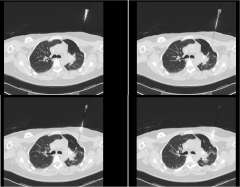

Planning begins with diagnostic imaging to help locate the tumor and determine the area that will be treated. This includes four-dimensional imaging that maps the target area as it moves over time with the patient’s breathing cycle. In the only invasive part of the treatment, gold seeds, called fiducials, are sometimes implanted into the tumor before images are taken. Because the fiducials are visible in planning scans and at the time of treatment, physicians use them to ensure that the high-dose envelope of radiation is accurately overlying the tumor.

SBRT requires highly accurate, precise, and focused radiation delivery in order to be successful because of the high dose of the treatment and the rapid radiation dose drop-off. It utilizes the same principles that have allowed radiation oncologists and neurosurgeons to successfully deliver highly focused and precise radiation treatment to brain tumors and brain metastases. Unlike the CNS, however, tumors and organs throughout the body can potentially move with breathing and other factors. SBRT treatments require accurate and precise tumor localization at the time of radiation simulation (Figure 4). Our expert team works closely with our interventional radiologists or surgeons to place fiducials (tiny gold seeds, or coils) into a patient's tumor in as minimally invasive a way as possible. These fiducials act as localizing and tracking devices (Figure 5). Fiducials assist us in targeting the tumor more accurately and precisely. The placement of fiducials is a procedure much like obtaining a biopsy for the tissue diagnosis of the cancer and is safely performed under image-guidance.

SBRT requires accurate and custom mapping for each individual patient's anatomy and organ motion so that we may be able to optimally target the tumor and simultaneously spare the surrounding normal tissue. We utilize any and all potential imaging modalities such as PET, MRI, CT, as well as other novel imaging platforms to localize the tumor in four dimensions. It requires highly sophisticated radiation delivery systems not available in most radiation oncology practices. More importantly, it requires clinical expertise and experience which allow our expert radiation oncologists to make sound treatment judgments regarding a recommendation for SBRT. In addition, you can be assured that our expert team will competently follow-through with an efficacious and safe SBRT radiation plan at the time of treatment. Instead of several weeks of conventional radiation therapy, patients complete their SBRT in a short-period of time, usually over a one week period, minimizing the inconvenience of daily trips to the radiation oncology facility.